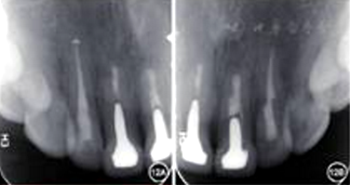

6.再治療術(shù)后2年復(fù)查:

見圖12,圖13。臨床檢查叩診正常,不松動(dòng),牙齦色澤正常,切口位置可見隱約瘢痕。根尖X線片顯示根尖無明顯病變。

圖12 術(shù)后2年復(fù)查患者根尖X線片 A:根尖無明顯病變;B:根尖無明顯病變